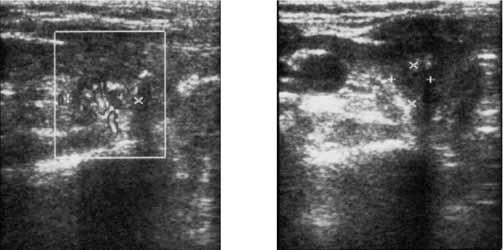

Náhlé zvětšování uzlu v polynodózní strumě je rovněž potenciálně maligní (až v 21%). Někdy se prokáže ca při punkci opakovaně se zvětšujícího cystického útvaru štítné žlázy. Riziko přítomnosti malignity je v solitárních uzlech vyšší než v polynodózních žlazách (3,5,8). Dominantní postavení v diagnostice ca štítné žlázy má ultrazvukové vyšetření. Zásadní význam má sonografie pro vyhledávání krčních metastatických uzlin. Lze prokázat i metastázy velikosti 5-10mm palpačně nepostižitelné (10). Diagnózu maligního uzlu štítné žlázy podporuje krátká anamnéza s uváděným rychlým růstem, jeho tuhost, snížená echogenita uzlu, laločnaté polycyklické ohraničení a nižší objem uzlu, který již působí klinické obtíže. Aspirační cytologie tenkou jehlou (FNAB) je nejspolehlivější diagnostická metoda pro odlišení maligních a benigních uzlů. Její senzitivita se uvádí více jak 90%, její specificita je 75% (2,5,10). Ke strumektomii jsou indikovány nálezy papilárního ca nebo podezřelé z malignity a všechny folikulární neoplazie (nelze pomocí FNAB odlišit folikulární adenom a karcinom). Definitivní histologie je stanovena až po chirurgickém výkonu na žláze. V některých případech je vodítkem diagnostická exstirpace krční uzliny (10). Scintigrafická (s 99mTc-technecistanem a 201Thaliem), kterými lze štítnou žlázu zobrazit a ověřit funkčnost uzlů, nepatří do běžného algoritmu vyšetření. Diagnostická scintigrafická vyšetřeními s nádorově specifickými radiofarmaky (99mTc-MIBI a 131J)jsou využívána v průběhu léčby a poléčebném sledování (10,11).

UZ vyšetření krku a eventuelně břicha.